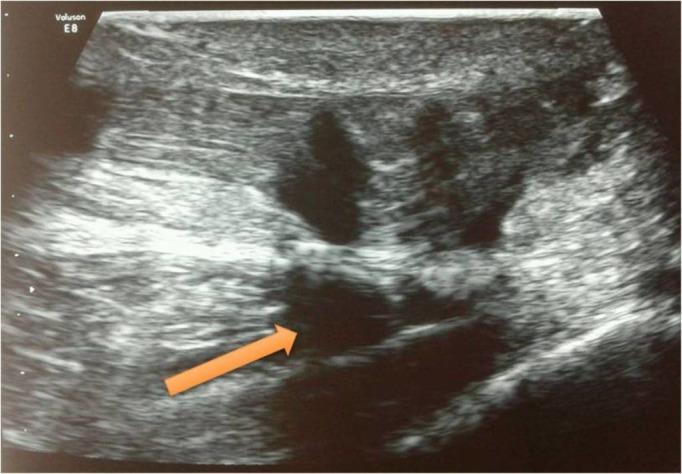

The Achilles tendon is the strongest tendon in the body, which is commonly ruptured in male athletes. Bilateral rupture of the Achilles tendon is a rare condition with very few reported cases in the literature. It poses a challenge in management, and hence, we report a case with traumatic bilateral Achilles tendon rupture in a young male patient and its management. One side was treated conservatively as the rupture was partial and the other side, which had a complete tear, was operated. At nine months follow-up, the patient has had a satisfactory result and is now bearing full weight without any problems. We suggest this method of treatment to be worthwhile for this unusual entity.

跟腱是人体最强壮的肌腱,在男性运动员中常发生断裂。双侧跟腱断裂是一种罕见的情况,文献报道的病例很少。它在治疗上具有挑战性,因此,我们报告一例年轻男性患者创伤性双侧跟腱断裂及其治疗情况。一侧因断裂为部分性而采用保守治疗,另一侧完全撕裂则进行了手术。在九个月的随访中,患者取得了满意的结果,现在能完全负重且没有任何问题。我们认为这种治疗方法对于这种不寻常的情况是值得的。